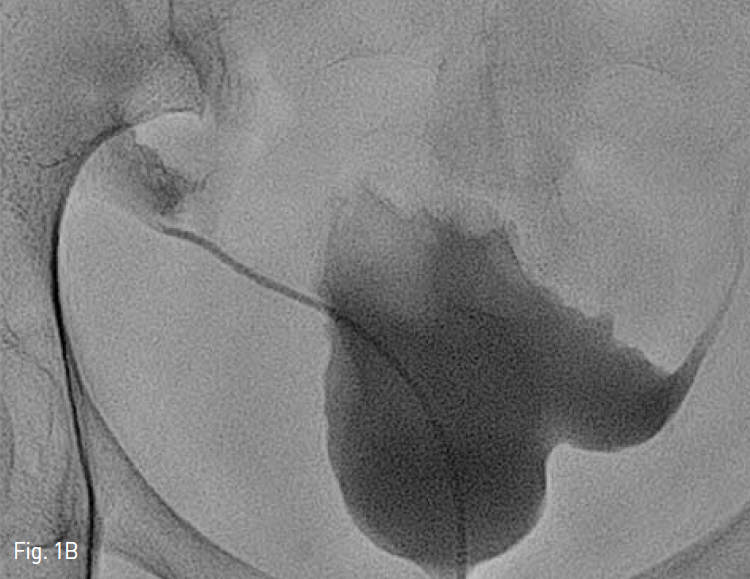

Fig. 1A, B

A-B. Antegrade nephrogram through PCN catheter and retrograde nephrogram through 5-Fr Kumpe catheter show stenosis at distal portion of left ureter with large amount of contrast leakage into the retroperitoneum.